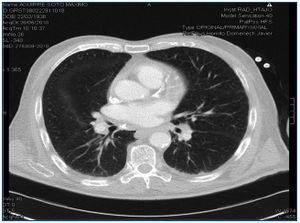

Tres años antes de iniciar la HD, y con tratamiento que incluía tiazidas y calcitriol oral, ingresó en otro hospital por hipercalcemia grave (hasta 13,5 mg/dl), con síntomas neurológicos y digestivos. En el estudio subsiguiente se demostraron adenopatías hiliares de tamaño no patológico y opacidades parenquimatosas pulmonares reticulares aisladas; hepatosplenomegalia homogénea; enzima de conversión de la angiotensina (ECA) en el límite elevado de la normalidad (tres determinaciones comprendidas entre 30 y 60 U/l, en condiciones normales, CN, 8-55). El resto del estudio fue negativo, por lo que el paciente fue diagnosticado de intoxicación exógena por vitamina D y tiazidas, y fue tratado mediante la administración de pamidronato parenteral, con una excelente evolución clínica. No constan niveles de 1-25 (OH)2 vitamina D3. Desde entonces ha permanecido asintomático, con hormona paratiroidea intacta (PTHi) suprimida y con tendencia espontánea a hipercalcemia límite, por lo que fue diagnosticado de enfermedad ósea adinámica (EOA). Durante el mes de julio de 2009 sufre un cuadro progresivo de astenia, anorexia, sudoración nocturna, desorientación, irritabilidad, alteración mnésica, apatía, apraxia y dificultad motora para la marcha. Se objetivan atrofia córtico-subcortical, leucoaraiosis y dilatación del sistema ventricular; tras realizar una punción lumbar con resultados bioquímicos y microbiológicos negativos se descartan hidrocefalia normotensiva, enfermedad infecciosa y degenerativa del sistema nervioso central (SNC). El cuadro se justifica por encefalopatía de pequeño vaso y con tratamiento conservador evoluciona hacia la cronicidad de forma lenta. No se administraban calcio oral, vitamina D ni derivados, y era dializado mediante un baño de calcio de 2,5 mEq/l. En mayo de 2010 presenta, sin variación clínica, hipercalcemia franca con valores máximos de 12,2 mg/dl y PTHi de 6 pg/ml (figura 1). Se realiza estudio complementario con los siguientes resultados: perfil tiroideo normal, Mantoux negativo (Booster negativo), radiografía de tórax indicativa de enfermedad pulmonar obstructiva crónica (EPOC); péptido asociado a la hormona paratiroidea (PTHrp) normal; fosfatasa alcalina normal; niveles de 25 (OH) vitamina D inferiores a 10 pg/ml; proteinograma e inmunoelectroforesis de proteínas plamáticas normales; inmunología negativa; gammagrafía ósea y serie ósea con osteopenia y calcificaciones vasculares, sin imágenes de osteólisis, marcadores tumorales normales y ECA de 157 U/l. En la tomografía computarizada (TC) de cuerpo entero se observaron múltiples adenopatías mediastínicas e hiliares bilaterales (figura 2). Los campos pulmonares presentaban un aumento de densidad «en vidrio deslustrado» de morfología nodular en el lóbulo medio; adenopatías en el tronco celíaco, perigástricas, periportales y en los espacios interaortocava y paraaórticos izquierdos; espirometría con alteración ventilatoria mixta de predominio restrictivo.

Figura 2. Tomografía computarizada de tórax. Adenopatías hiliares.